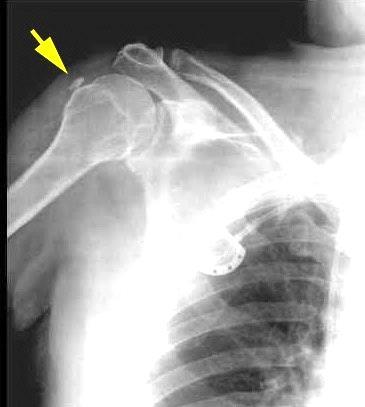

30. HOMBRO. TUMOR DE CÉLULAS

GIGANTES